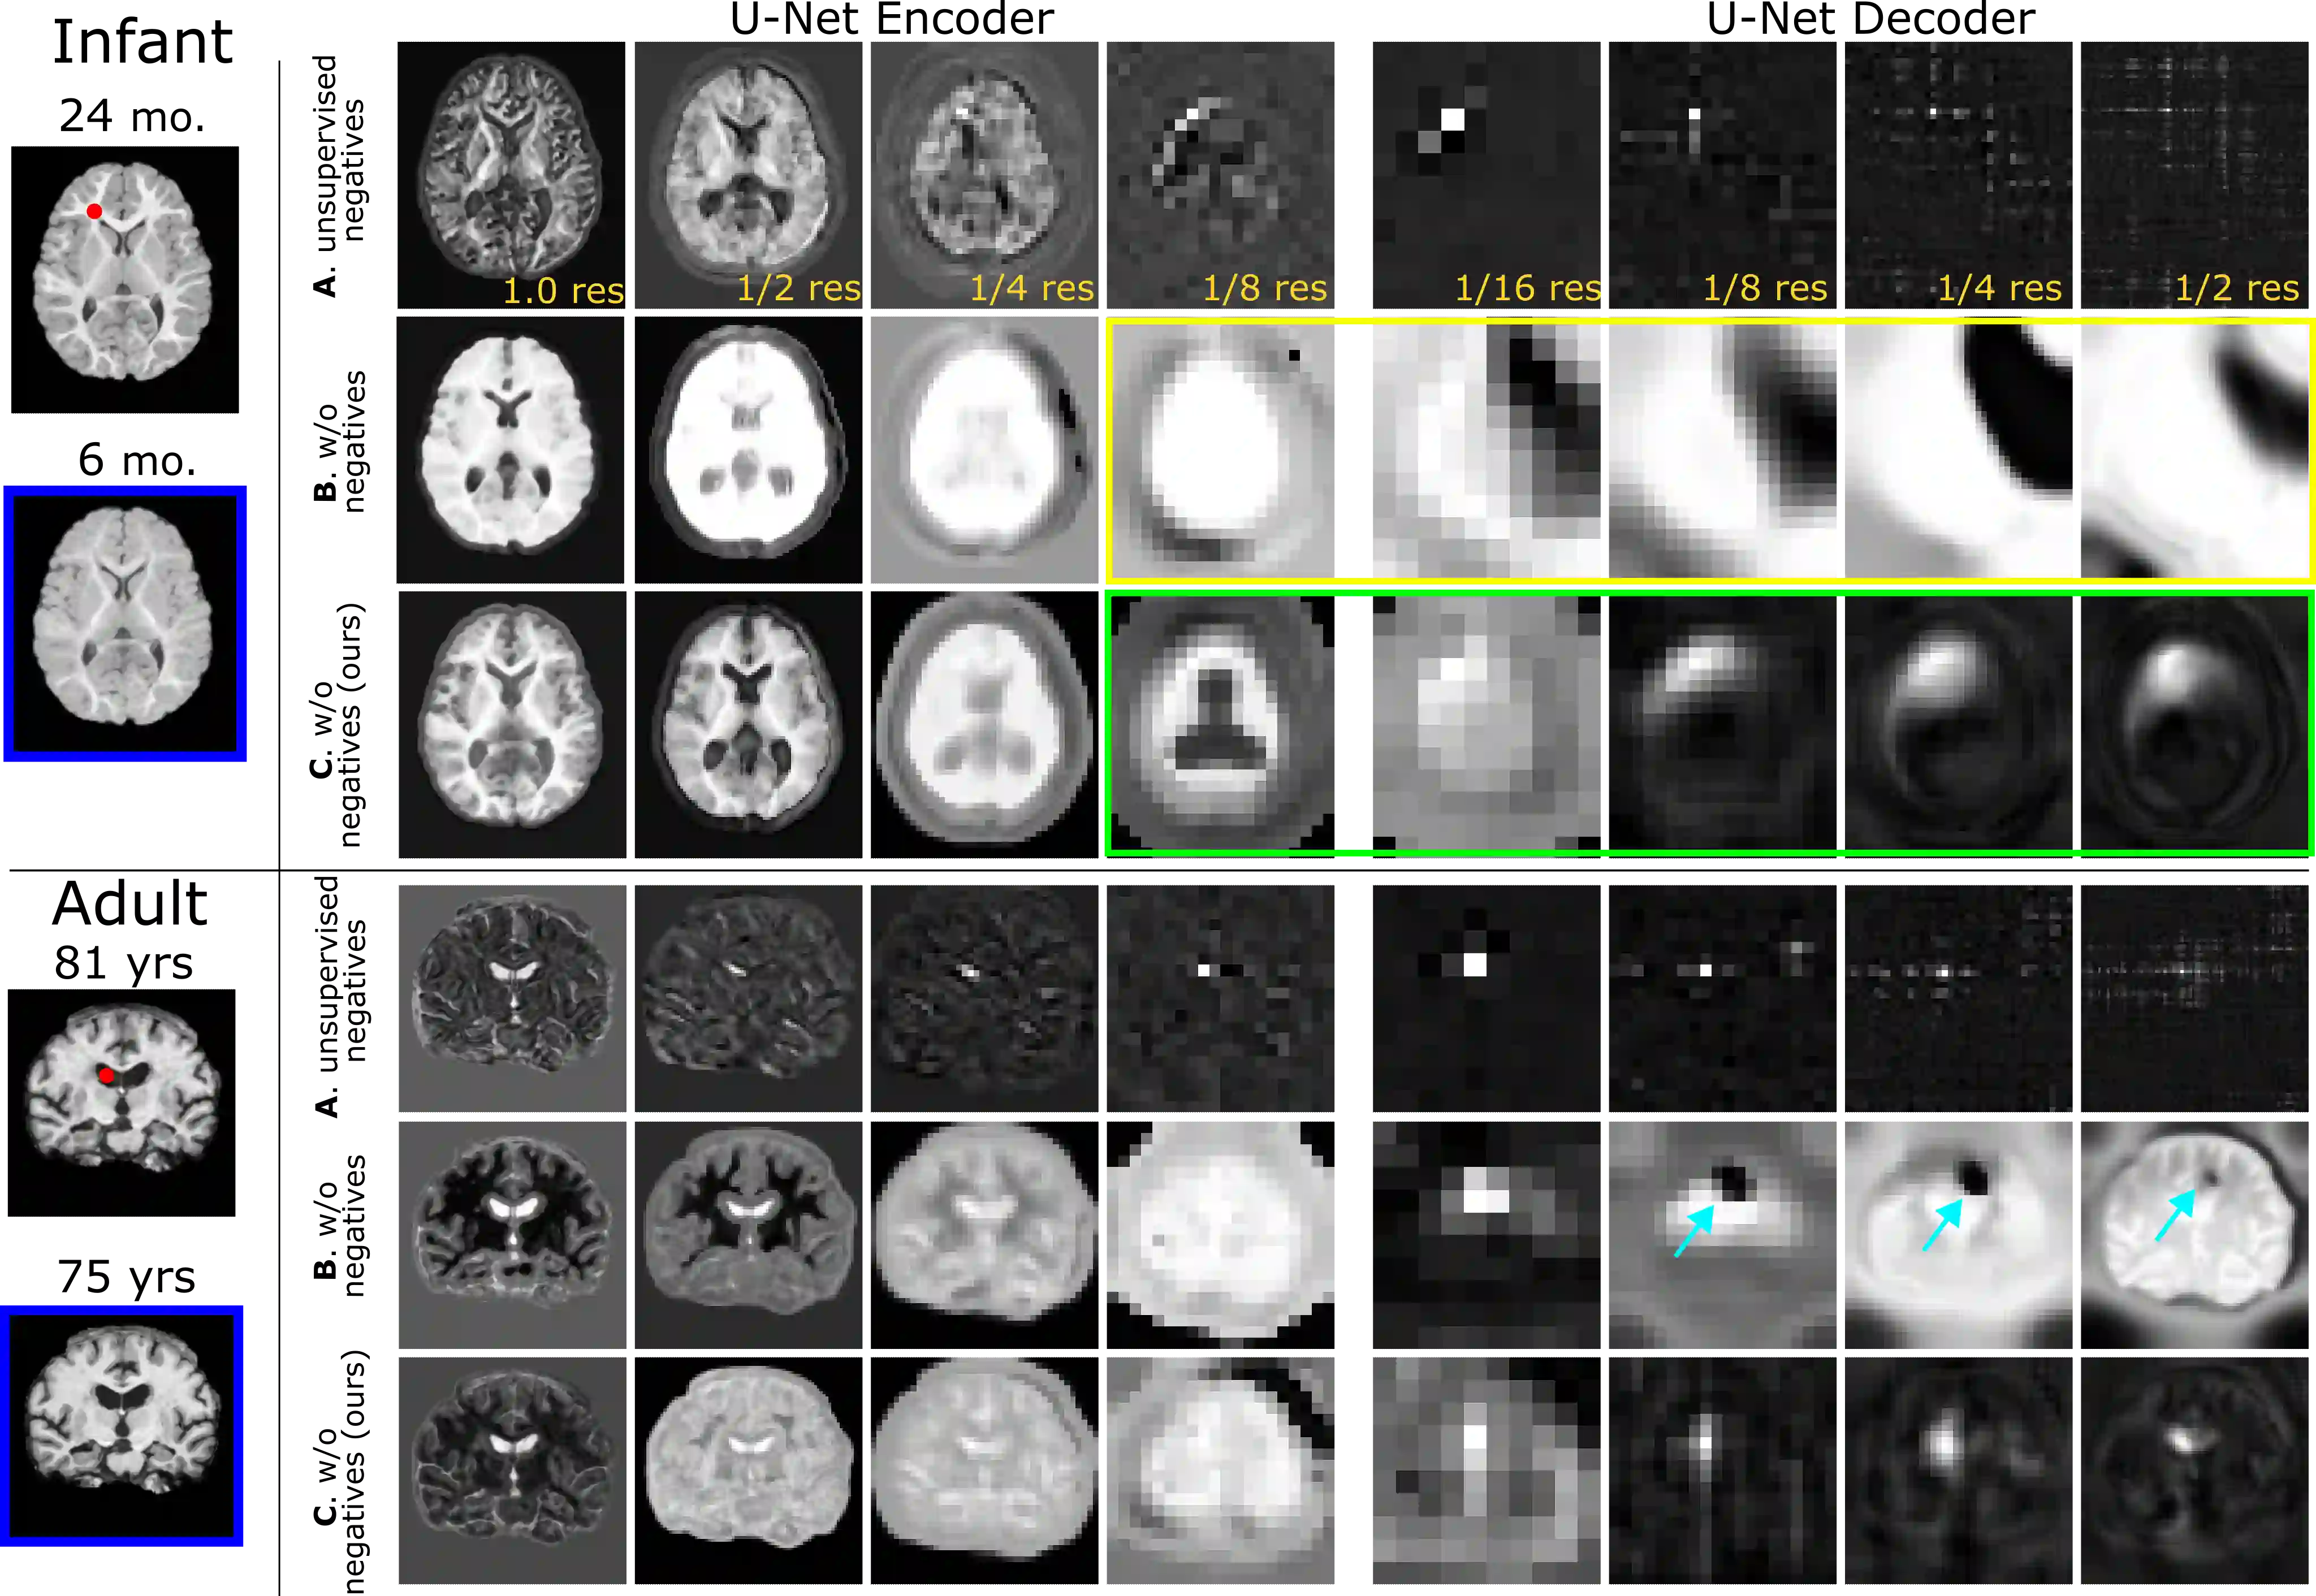

Recent self-supervised advances in medical computer vision exploit global and local anatomical self-similarity for pretraining prior to downstream tasks such as segmentation. However, current methods assume i.i.d. image acquisition, which is invalid in clinical study designs where follow-up longitudinal scans track subject-specific temporal changes. Further, existing self-supervised methods for medically-relevant image-to-image architectures exploit only spatial or temporal self-similarity and only do so via a loss applied at a single image-scale, with naive multi-scale spatiotemporal extensions collapsing to degenerate solutions. To these ends, this paper makes two contributions: (1) It presents a local and multi-scale spatiotemporal representation learning method for image-to-image architectures trained on longitudinal images. It exploits the spatiotemporal self-similarity of learned multi-scale intra-subject features for pretraining and develops several feature-wise regularizations that avoid collapsed identity representations; (2) During finetuning, it proposes a surprisingly simple self-supervised segmentation consistency regularization to exploit intra-subject correlation. Benchmarked in the one-shot segmentation setting, the proposed framework outperforms both well-tuned randomly-initialized baselines and current self-supervised techniques designed for both i.i.d. and longitudinal datasets. These improvements are demonstrated across both longitudinal neurodegenerative adult MRI and developing infant brain MRI and yield both higher performance and longitudinal consistency.